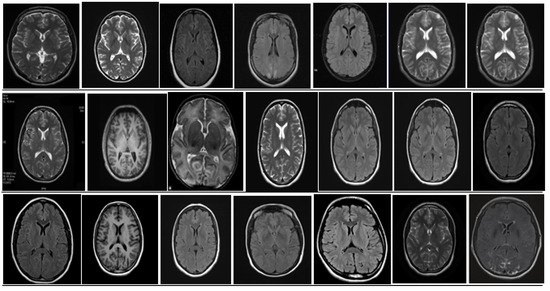

5. Database and Dataset

5.1. DataBase Collection

| Dataset | Number of Images |

|---|---|

| Original dataset | 253 |

| Tumor brain MRI images | 155 |

| Non-tumor MRI images | 98 |

| After augmentation | 3700 |

| Training | 185 |

| Validation | 48 |

| Test | 20 |